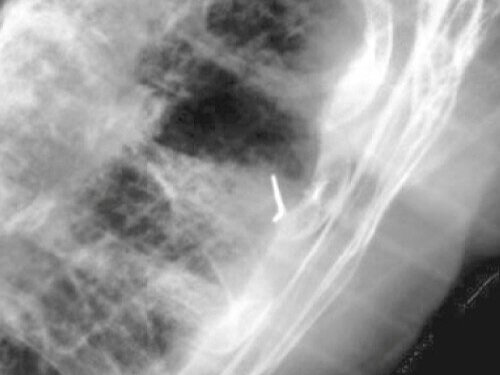

0.75mm x 0.5cm Visicoil MR (Implanted for a CyberKnife Treatment)

GE Discovery CT with 1.25mm per slice (512 total slices, no tilt, no overlap, & no gap)

GE MR750W 3.0T 1.3mm per slice (about 180 total slices, no overlap & no gap). 3.0 Tesla with scans of the Pulse Sequences (scan techniques) of T2, T1 with & without contrast.